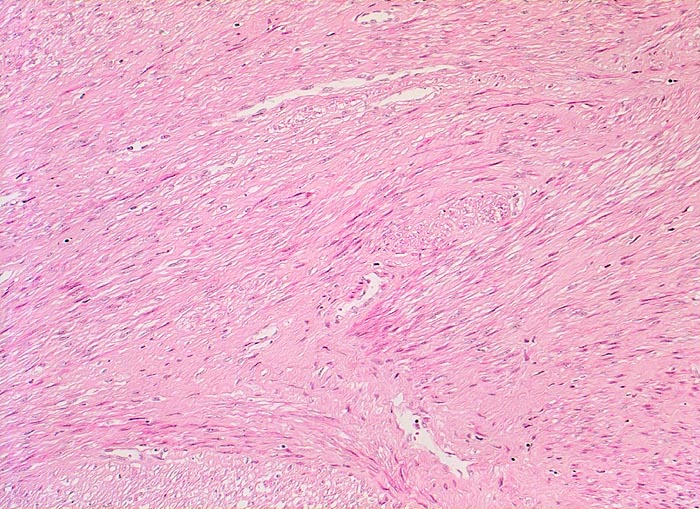

Myome imponieren makroskopisch typischerweise als runde, scharf begrenzte und nicht bekapselte Knoten. Die Schnittfläche ist weiss mit wirbliger Struktur. Mikroskopisch ist der Tumor aufgebaut aus Bündeln (=Faszikeln) spindelförmiger Zellen mit reichlich dunkel-eosinophilem Zytoplasma und an den Enden abgerundeten länglichen, zigarrenförmigen Kernen. Zell- und Fasergehalt sind sehr variabel. Degenerative Veränderungen wie Verkalkungen (> 4280), hyaline Nekrosen, Einblutungen, Homogenisierung des Kollagens, Ödem oder myxoide Degeneration und Zystenbildung (> 4279) kommen häufig vor. Manche gutartigen Leiomyome können ein einzelnes Malignitätskriterium aufweisen (vermehrte Mitosen, hohe Zellularität, deutliche Zellatypien oder Nekrosen). Falls mehr als eines dieser Kriterien vorhanden ist, handelt es sich differentialdiagnostisch um einen leiomyomatösen Tumor mit unsicherem Malignitätspotential (STUMP=Smooth Muscle Tumor of Uncertain Malignant Potential) oder um ein Leiomyosarkom. In seltenen Fällen lässt sich die Dignität nicht sicher bestimmen.

Morphologische Merkmale:

• Zwei scharf begrenzte Knoten im Myometrium bestehend aus Bündeln glatter Muskulatur.

• Variabler Anteil Fibrose (Kollagenfasern).

• Glatte Muskelzelle: eosinophiles Zytoplasma, längliche Kerne mit abgerundeten Enden (zigarrenförmig).

• Keine signifikanten Zellatypien. (signifikant=bereits in der Übersichtsvergrösserung erkennbar).

• Keine Mitosen.

• Keine Tumornekrosen.